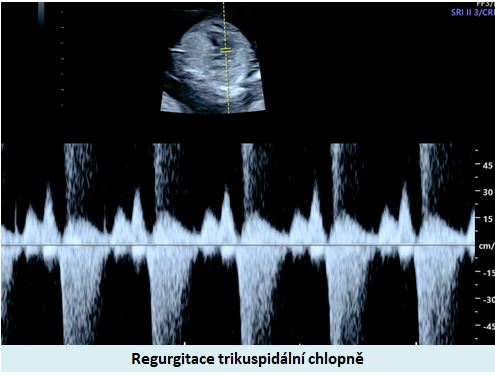

Ultrazvuková diagnostika se při screeningu v 1. trimestru opírá o šířku podkoží v záhlaví plodu, osifikaci nosní kůstky a nálezu abnormálních průtoků v srdci plodu (trikuspidální regurgitace, reversní tok v ductus venosus).

Pracoviště se zkušenostmi v prenatální diagnostice a s dobrým přístrojovým vybavením je schopno vyslovit podezření na tento syndrom ve více jak 90% případů již při ultrazvukovém vyšetření ve 12-13. týdnu těhotenství. .